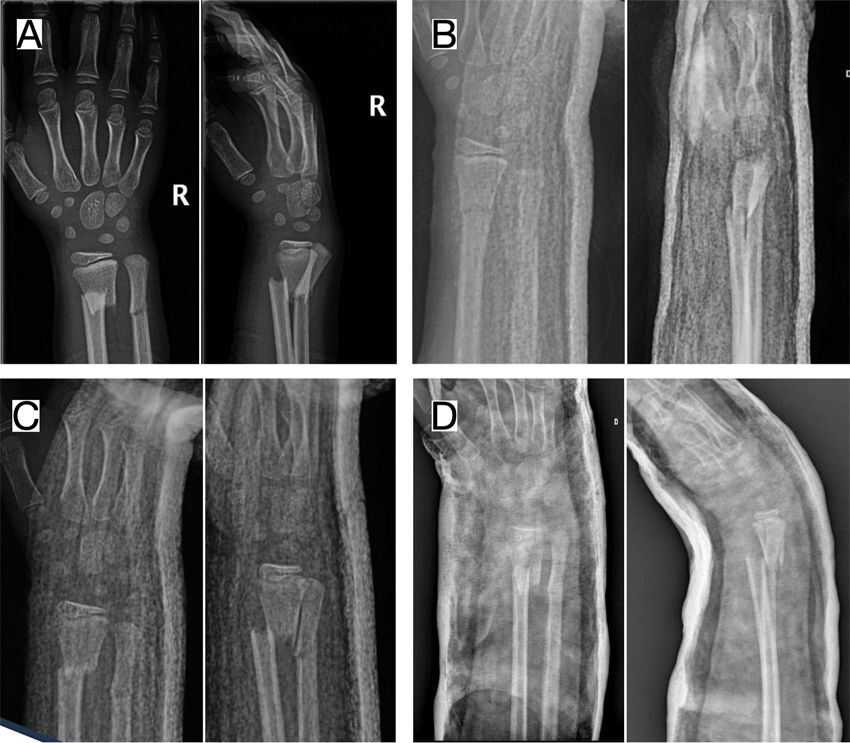

As specialists in a nationally designated Reference Center for Pediatric Orthopaedics and Traumatology, we frequently treat children with overriding metaphyseal distal radius fractures, with bayonet apposition, who have undergone multiple reduction attempts under sedation or anesthesia at other centers—often repeatedly, due to unsatisfactory reductions or loss of alignment. These fractures are often stabilised using Kirschner wires, or in some cases via open reduction and plate fixation. Many of these patients seek a second opinion and present with swelling pain, or even potential risk of compartment syndrome due to excessively tight casts or immobilisation in extreme, unnecessary positions (Fig. 1). Such practices, still common in many departments and often extrapolated from adult fracture care, contrast sharply with recent evidence and accumulated clinical experience, both of which increasingly support a more conservative approach in preadolescent children.

Clinical case of a 6-year-old patient with a displaced and overriding distal radial metaphyseal fracture treated at a different centre. (A) Initial X-ray after accidental trauma, showing an overriding fracture. (B) Follow-up with closed cast after initial reduction at another centre. Consultation the following day due to severe pain and digital swelling. (C) Follow-up after 10 days, showing loss of reduction. (D) X-ray after re-manipulation and placement of a cast in extreme volar flexion; as reduction was not achieved, the family were offered surgical treatment.